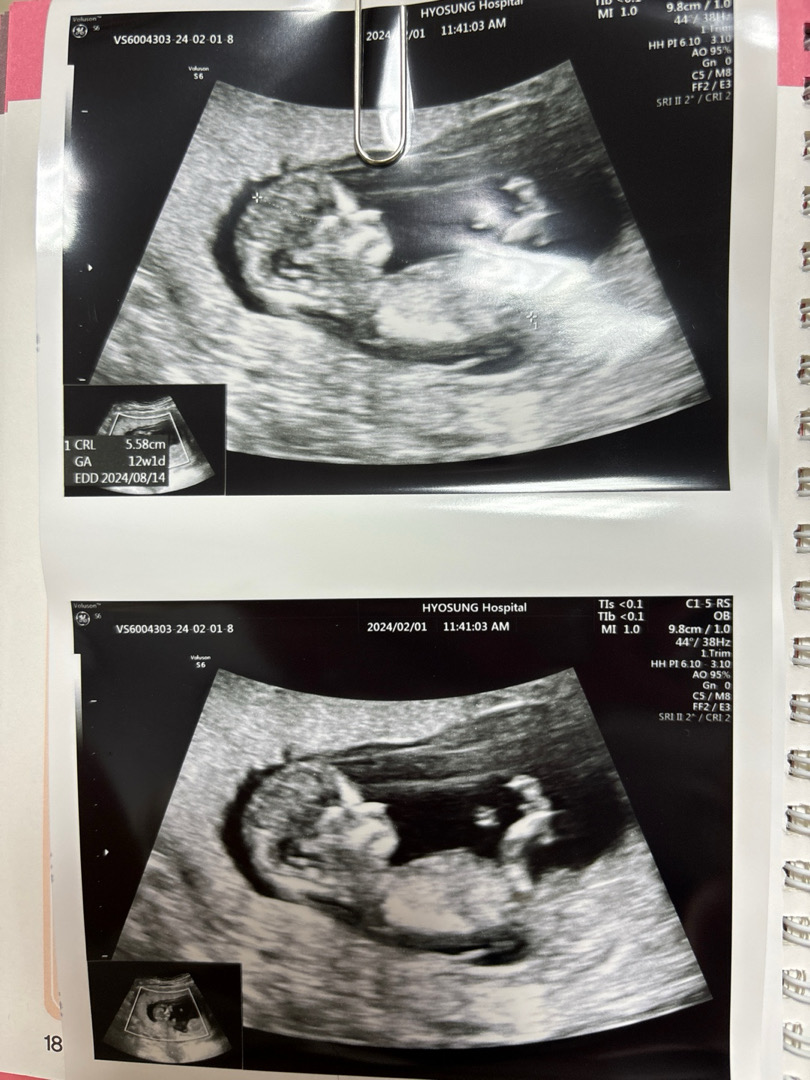

12주 각도법

콧대가 엄청 높져?😁😁😁 하루하루 시간이 너무 느리게 가는거같아요🥲 12주 기형아검사 100점받고 와서 기분이좋아요 성별 혹시 알수있는지 의사쌤께 여쭤봤더니 우리껌딱지가 다리를 꼬고 공개를 안해주네용😩😩 16주 한달을 더기다리려니 딸인지 아들인지 너무궁금해요😂😂 누워있는자세로도 알수있다하던데 어때보이나용?